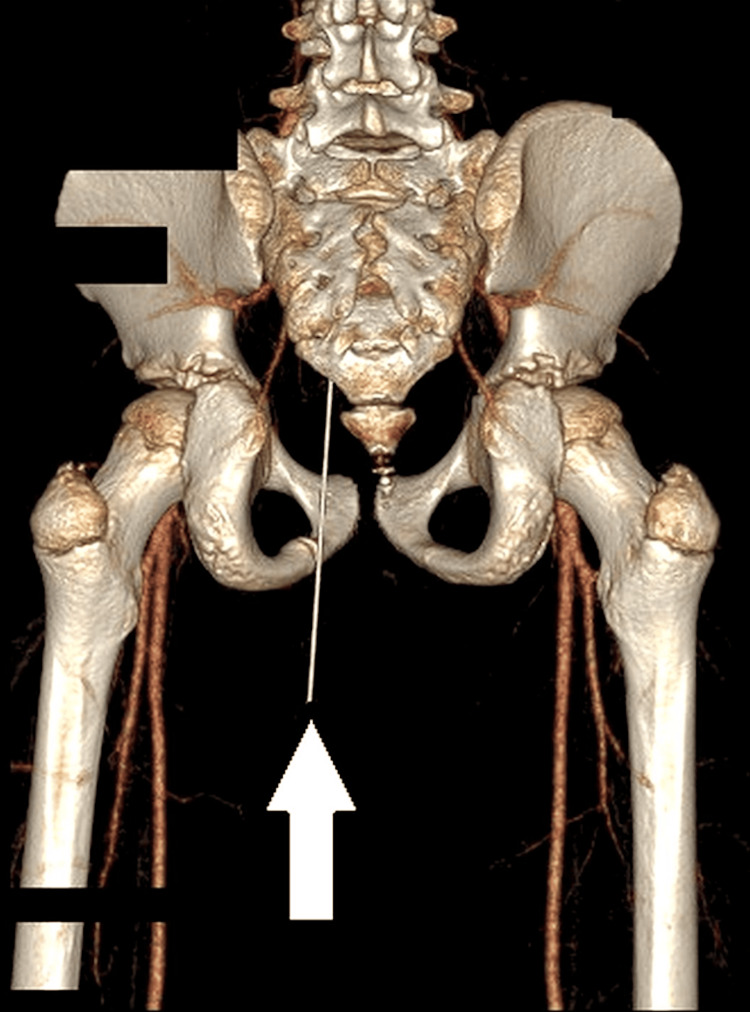

Pensel termasuk ke dalam gluteal sejauh 12.4cm

Walaupun nampak seperti tidak kritikal secara luaran, sebenarnya objek berkenaan telah menembusi daging punggung (gluteal) murid berkenaan sedalam 12.4cm. Imbasan seterusnya turut mengesahkan hujung pensel terbabit sudah terkena pada bahagian rektum (bahagian akhir usus besar).